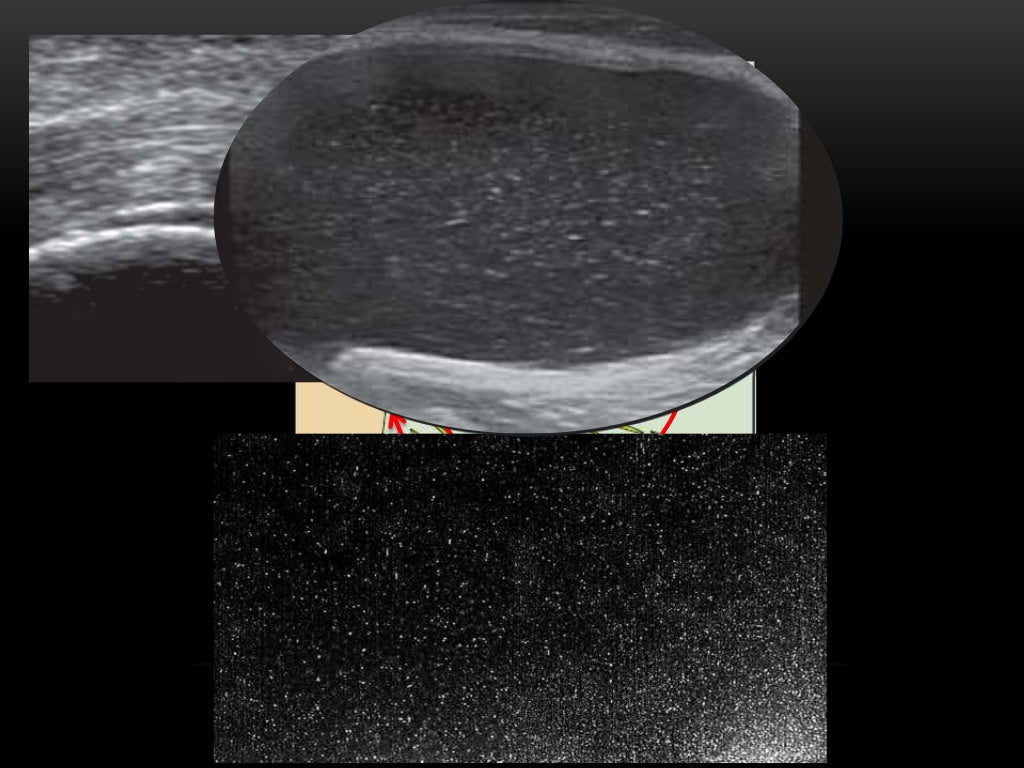

Crystal arthropathies; Pearls for MSK Ultrasound practitioners

From sonotool.net

Crystal arthropathy SonoTool® Crystal Arthropathy Examples the most common crystal arthropathy, is caused by monosodium urate crystal precipitation and appears to be increasing. gout and pseudogout are crystal arthropathies. crystal arthropathies are a group of joint disorders due to the deposition of crystals in and around joints which lead to joint destruction and soft. Crystals of urate (in gout) and calcium pyrophosphate (in. Crystal Arthropathy Examples.